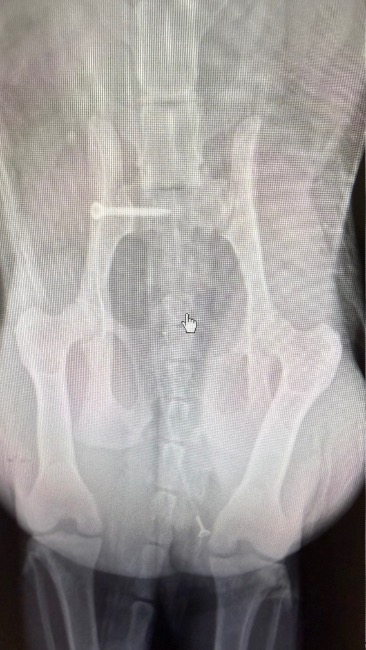

Dostaliśmy zgłoszenie z gminy Liszki o kotce potrąconej przez samochód. Gmina odmówiła pomocy, nie mają pieniędzy na takie zabiegi, zwierzęta często poddawane są eutanazji. My nie mogliśmy odmówić. Sytuacja była pilna. Okazało się, że kotka na złamaną miednicę. Przed zabiegiem musiała mieć przetoczoną krew, parametry czerwonokrwinkowe nie pozwalały na znieczulenie. Bardzo dziękujemy dziewczynom z fundacji Stawiamy na łapy, za natychmiastową pomoc, jeszcze tego samego dnia udało się znaleźć dawcę krwi i wzmocnić kotkę przed zabiegiem. Pimpa miała też wielkie szczęście, bo udało się znaleźć termin na CITO u świetnego ortopedy dr Rafała Korty z lecznicy Arwet, który złożył jej miednicę. Na chwilę obecną kotka jest bardzo słaba, ale dzielnie walczy. Niestety nie sika samodzielnie, jest cewnikowana. Nie chce też jeść, jest dokarmiana przez sondę. Za to parametry czerwonokrwinkowe poprawiają się. Czeka ją długa rekonwalescencja, przed nami jeszcze kastracja, oraz zabieg stomatologiczny, ale to dopiero po ustabilizowaniu stanu zdrowia. Dziękujemy też zespołowi Luxvet24 w Krakowie, za świetną opiekę zarówno przed, jak i po zabiegu. Bardzo prosimy o wsparcie, to dopiero początek walki o jej życie i zdrowie. Każda złotówka jest na wagę złota !